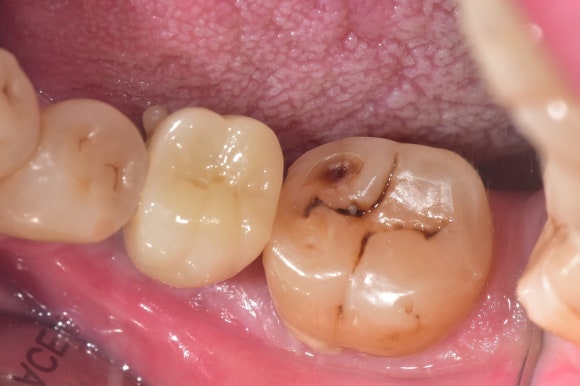

20250404

기둥에 크라운을 붙입니다.

절묘한 각도로, 매우 정밀한 크라운이 만들어졌습니다.